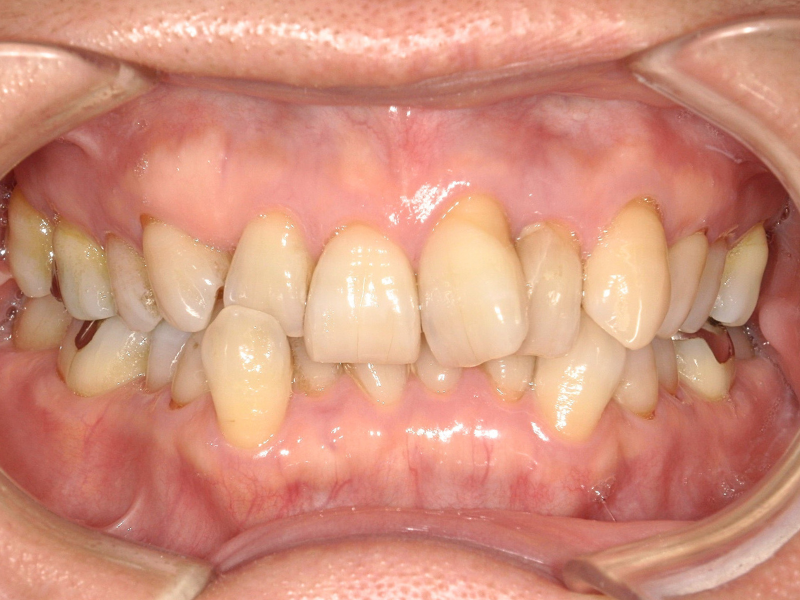

10代、女性、ワイヤー

| 施術内容 | 主訴:上下前歯でこぼこ。なるべく抜きたくない。 詳細:ワイヤー矯正での歯並び改善 詳細:ワイヤー矯正での歯並び改善 歯肉炎リスクあるため、今後は後戻りのチェックとともに歯肉炎管理もしていきます。 |

| 治療期間 | 12ヶ月(2/6現在 治療終了) |

| リスク・副作用 | ■リスク・副作用 ・治療の初期段階では、痛みや不快感が生じやすくなりますが、一週間前後で慣れます。 ・歯の動き方には個人差があるため、予想された治療期間より延長する場合があります。 |

| 費用 | ワイヤー矯正 60万円(税込660,000円) |